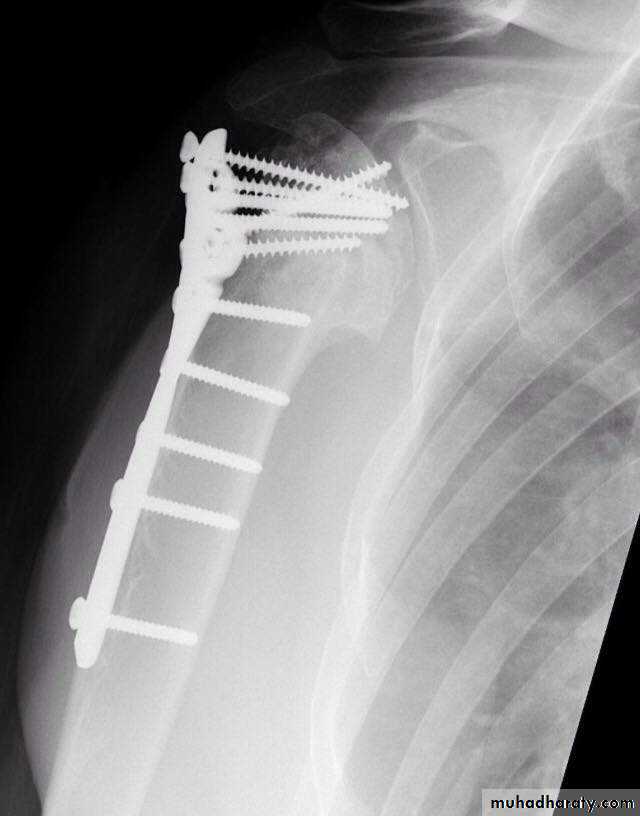

TREATMENT

30

ORIF

TRATMENT IN YOUNG

35